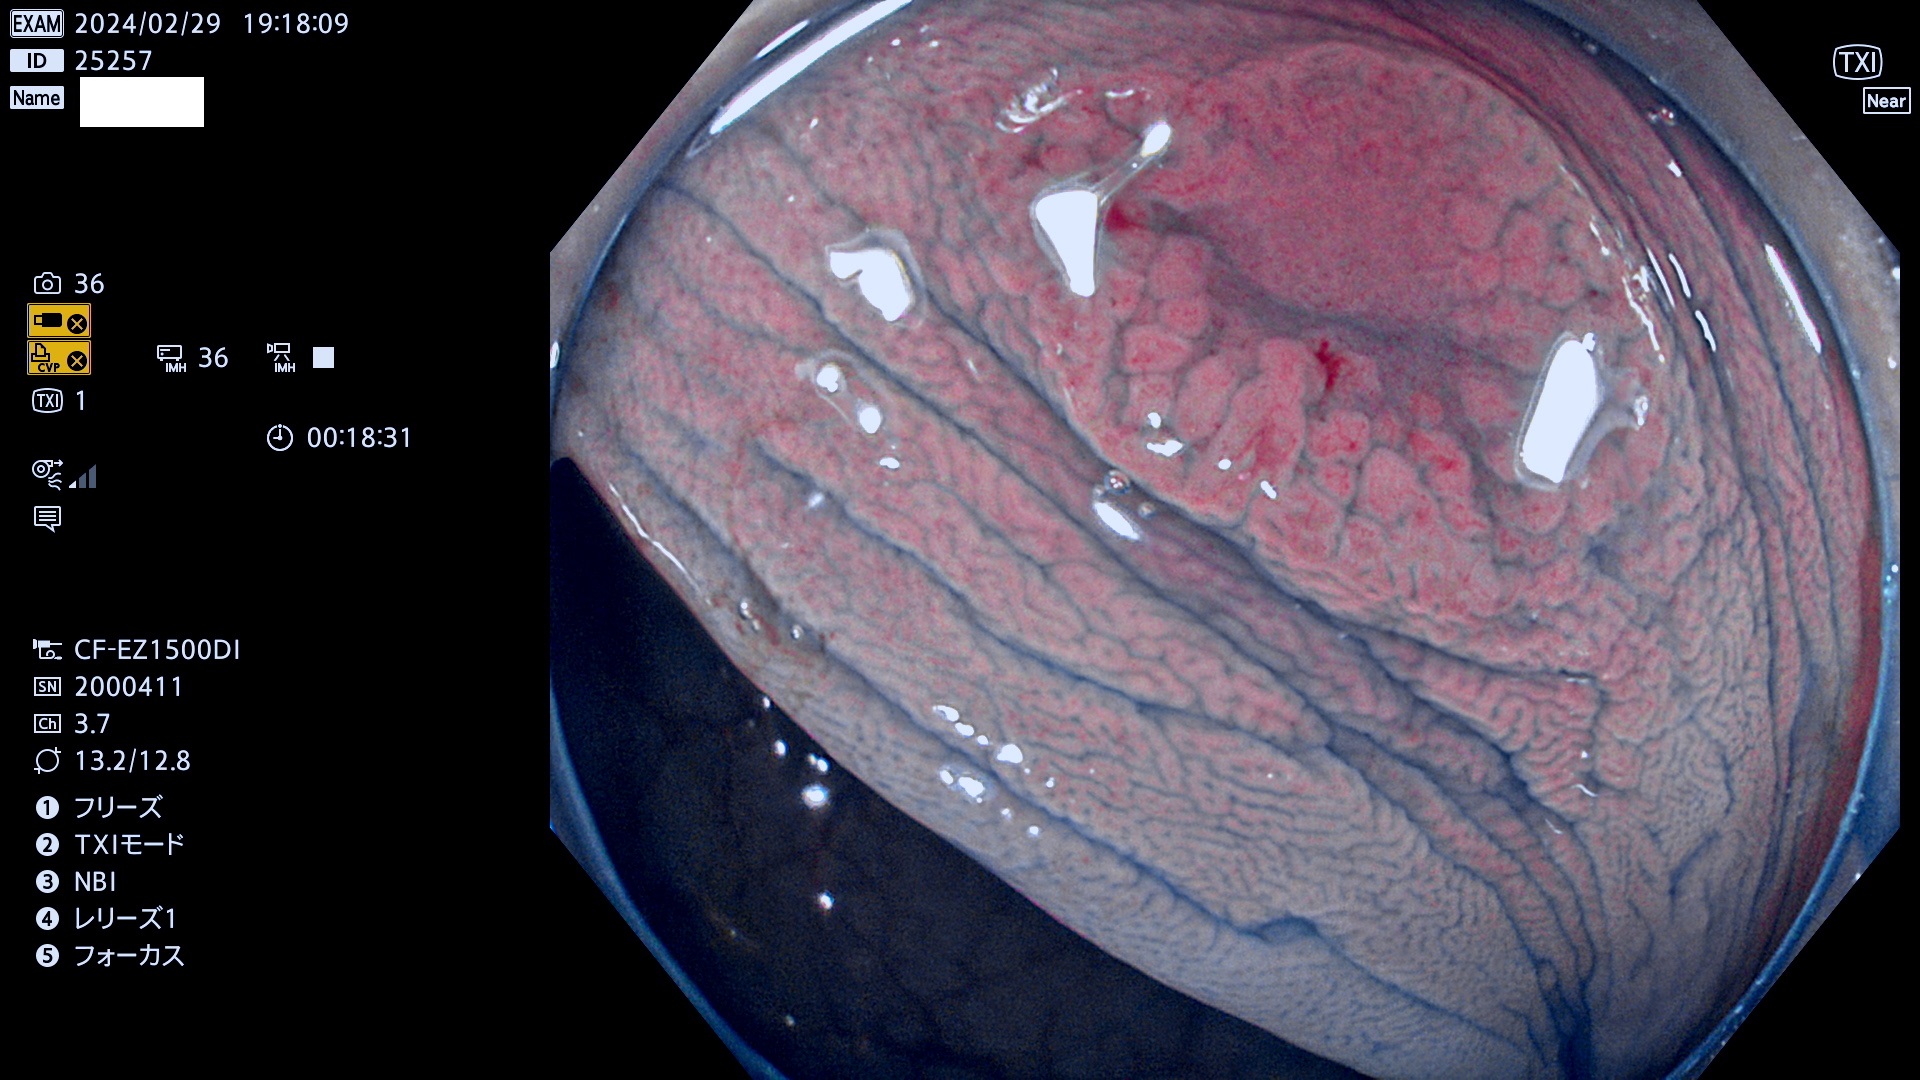

表面型腺腫(Flat Adenoma)の中で、完全に平坦な物をUb、陥凹している物をUcと呼びます。平坦隆起型(Ua)よりも、発見が難しく危険な病変です。

専門的)何故、陥凹していると危険? 癌遺伝子の変異が蓄積すると細胞分裂が盛んになり隆起するのでは?と通常は思われるでしょう。しかし実際は逆です。これは2022年の記事にある「細胞はストレスに直面したら細胞分裂を止める(細胞老化に入り休眠する)という生命の基本的現象」によるものです(Oncogene Stress)。細胞老化を起こすのが癌抑制遺伝子で、この安全装置(ブレーキ)が壊れると癌になります(休眠からの覚醒)。ですから陥凹は「まだ癌では無いが癌化の直前」を意味します。特に「小サイズなのに陥凹している」病変は短期間に腫瘍進化(⇒2021年記事)が起きたことを意味します(=ゲノム不安定性

専門的)Uc=De Novo癌? 内視鏡の解像度が低かった時代、このような説もありました。しかし今日の高精度内視鏡では良性の微小なUc型腺腫が日常的に見つかります。私見ですが「Ucこそが多段階発癌(Adenoma-Carcinoma Sequence)のMain Route」と考えます。

毎週の検査(木・金・土・日)に発見されたUb、Uc型・腺腫を、その週の日曜の夜にUPし1週間、提示します。

抽出の対象期間 2024年2月29日(木)〜3月4(日)の5日間(50件の検査)4件 (4/50=8%)